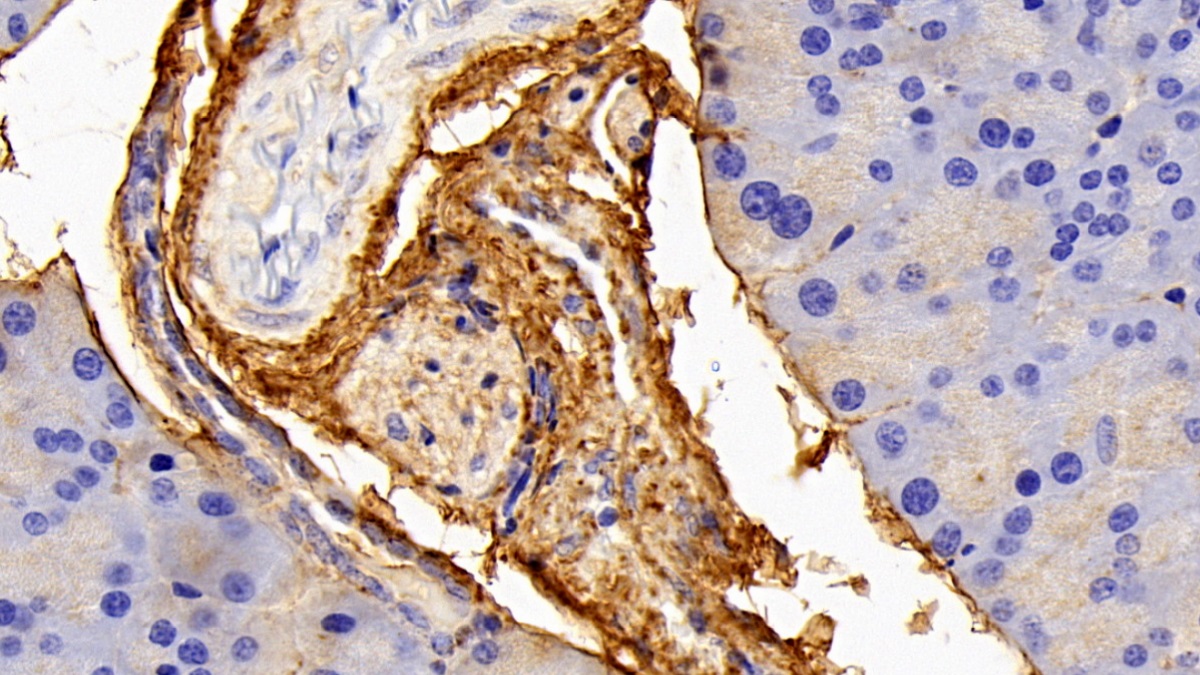

Использование высококачественных первичных антител является неотъемлемым условием получения точных и воспроизводимых результатов в современных научных исследованиях. Например, в рамках онкологического исследования удалось достоверно идентифицировать экспрессию белка PD-L1, что сыграло ключевую роль в оценке потенциальной эффективности иммунотерапии. Применение надежных антител обеспечило стабильность сигнала и высокую специфичность детекции, что позволило получить данные, пригодные для публикации в рецензируемых научных изданиях.

Первичные антитела используют в разных методах: от вестерн-блоттинга до иммунофлюоресценции и проточной цитометрии. Всё решает подготовка: нужно грамотно выбрать буфер, точно рассчитать, сколько продукта добавить, и не затянуть с инкубацией. Например, в вестерн-блоттинге без правильной блокировки мембраны фон может всё испортить, а в иммунофлюоресценции фиксация клеток решает, будет ли сигнал ярким. Мы не просто продаём реагенты, а помогаем довести эксперимент до результата: подбираем реагенты и даём советы по методам, если есть специфика в протоколах производителя. Нужен особый подход? Оформите спецзаказ по ссылке — мы найдём решение для вашего проекта.